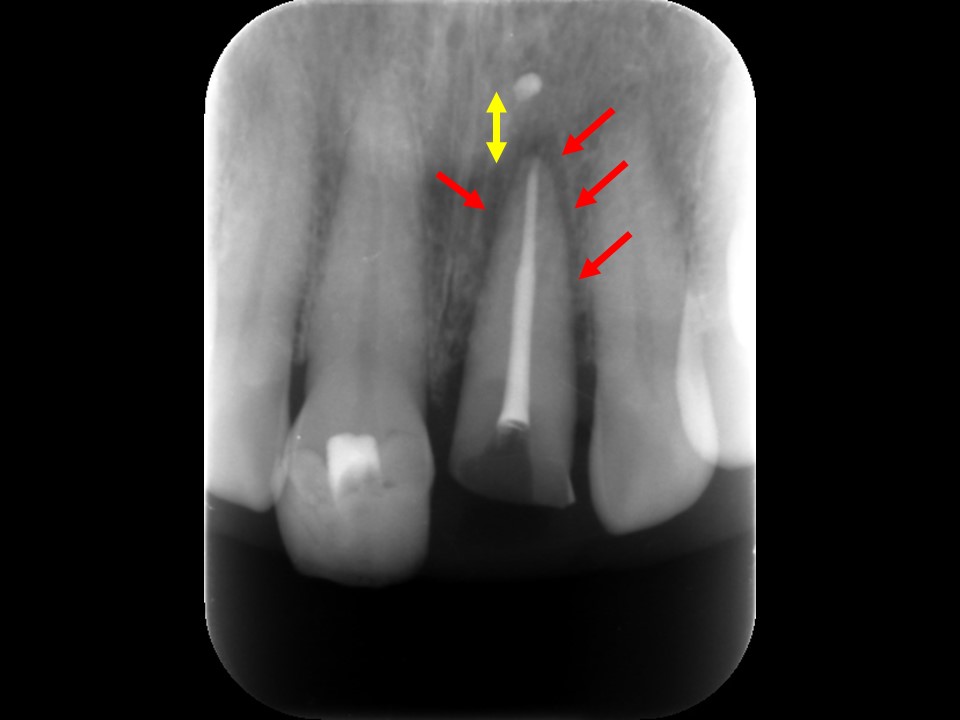

外科的挺出直後。歯根を約3㎜ほど外科的に歯槽骨から引き出した(黄⇒)。歯根が歯槽骨から脱臼されているため、歯根周囲は黒い隙間が確認できる(赤⇒)。歯の動揺が強いため、隣在歯と接着剤で固定を図る。